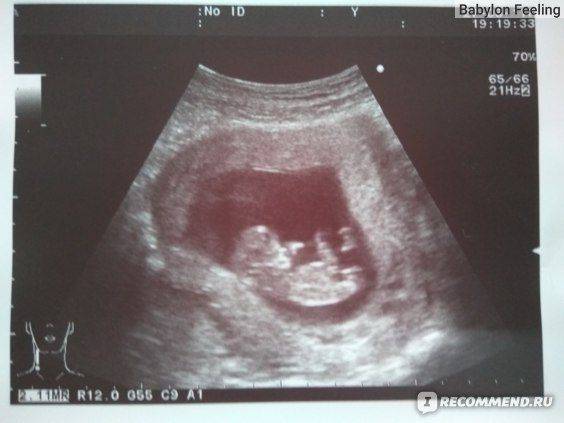

С чего всё началось? На 11-ой неделе у меня начало кровить. Пара капель, которые после приема Дюфастона прекратились. Я пулей на УЗИ. Всё нормально, но на сохранение я всё же легла. В больнице меня уже ничего не беспокоило, я наслаждалась отдыхом от работы и домашних дел. Пока мне не сделали УЗИ. Это было 11 недель и 1 день. В заключении — Мегацистис под вопросом. Коротко расскажу об этом диагнозе. Мегацистис — это увеличенный мочевой пузырь у плода. Может быть признаком синдрома Патау, либо врожденной аномалией моче-половой системы (например, не сформировалась дырочка, чтоб пописять). У моего малыша он был 7 мм, это верхняя граница нормы. Но, учитывая, что КТР 50 мм, то мочевой пузырь занимал 14% длины тела ребенка! На фото видно тёмное пятнышко между ножек.